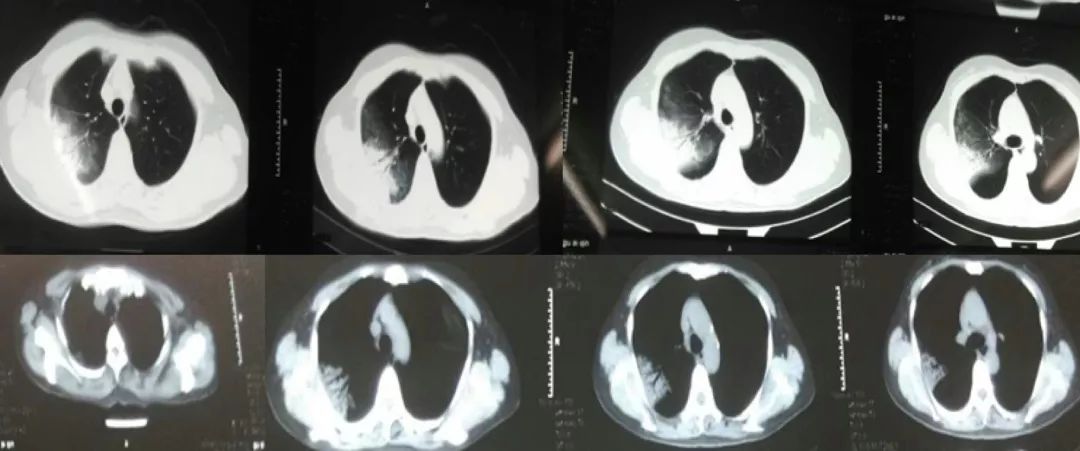

胸部CT:

2017-1-15

2017-1-23

2017-2-5

2017-3-5

患者起病时2017-1-15胸部CT病变主要在右肺上叶后段,表现为大片状高密度影,可见支气管气象,提示支气管内不是阻塞性病变,病灶内有实变,周围有渗出性改变,纵膈窗和肺窗差别比较大,说明病灶密度不是非常高;

2017-1-23胸部CT病灶从范围来看是逐步扩大的,仍可见支气管气象,周围渗出更加明显,纵膈窗来看病灶总体密度增高,影像学表现总体提示病灶进展;

2017-2-5胸部CT:整体病变范围与2017-1-23号CT变化不大,但整体密度呈减低趋势,纵膈窗影像密度与肺窗差别较大,说明病变呈好转趋势;

2017-3-5胸部CT右上肺大片状高密度影消散,仅留下少许高密度条索影,但左肺上叶后段出现新发病变,但与之前右肺上叶病变影像学特征有所不同,之前三次影像学病灶密度是比较均匀的,此次左肺上叶后段病变,除了实变之外可见类空洞样改变,仍有支气管充气征,周围见细条索影,右下肺背段见类结节影像。

> 影像学检查:起病表现为右上叶后段斑片状高密度影,伴部分实变,可见支气管充气征,抗感染治疗后右上叶病灶完全吸收,新出现左上肺团片影,周边磨玻璃影,及右下肺背段不规则团块影。